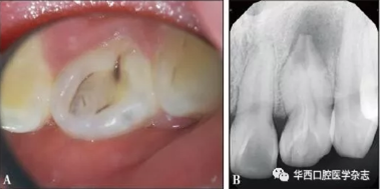

患者萬某,女,21歲,2017年3月26日因左上前牙偶發(fā)脹痛不敢咬合數(shù)年于南昌大學(xué)附屬口腔醫(yī)院牙體牙髓科首診??趦?nèi)檢查:22牙唇側(cè)牙冠顏色、形態(tài)無異常,舌側(cè)中央內(nèi)陷,下方呈黑褐色,舌隆突處凹陷未蔓延至齦下(圖1A),唇舌側(cè)牙齦色澤形態(tài)質(zhì)地均無明顯異常,未見瘺管,叩診陽性,牙周探診6個位點探診深度均小于3 mm,無附著喪失,無松動;牙髓電活力測試,12牙讀數(shù)17(上限64),21牙讀數(shù)20(上限64),22牙無反應(yīng);牙髓溫度測試,12牙、21牙冷熱診反應(yīng)一過性敏感,22牙冷熱診無反應(yīng)。X線片示22牙根管彎曲,牙冠內(nèi)陷從釉質(zhì)延續(xù)至根中1/3,主根管中央有一“內(nèi)陷小牙”高密度影結(jié)構(gòu),內(nèi)陷組織遠(yuǎn)中與主根管間可見明顯間隙,根尖孔粗大,根尖區(qū)為邊界不規(guī)則低密度影像,未見牙槽嵴頂處骨高度吸收異常(圖1B)。

A:口內(nèi)照;B:X線片。

圖 1 治療前情況